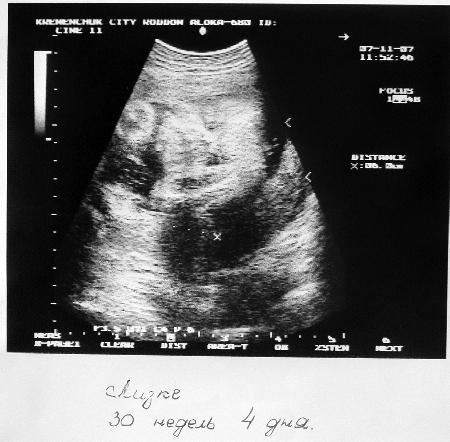

У Ані тихий голос і заплакані очі. Вона дуже молода – їй 18 років і вона студентка. Чоловік Ані теж студент. 9 січня у кременчуцькому міському пологовому будинку у них мала народитися Ліза. Вагітність проходила спокійно, без ускладнень. Ультразвукові обстеження засвідчували, що маленька Ліза теж здорова. Єдине, що непокоїло Аню та її родину – це «тазове передлежання» дитини (тобто маля йшло на вихід сідничками). Це стало відомо вже за два тижні до пологів. Тому Аня попросила лікаря Б. зробити кесаревий перетин. Про те саме просив і батько Ані. Лікар відмовив.